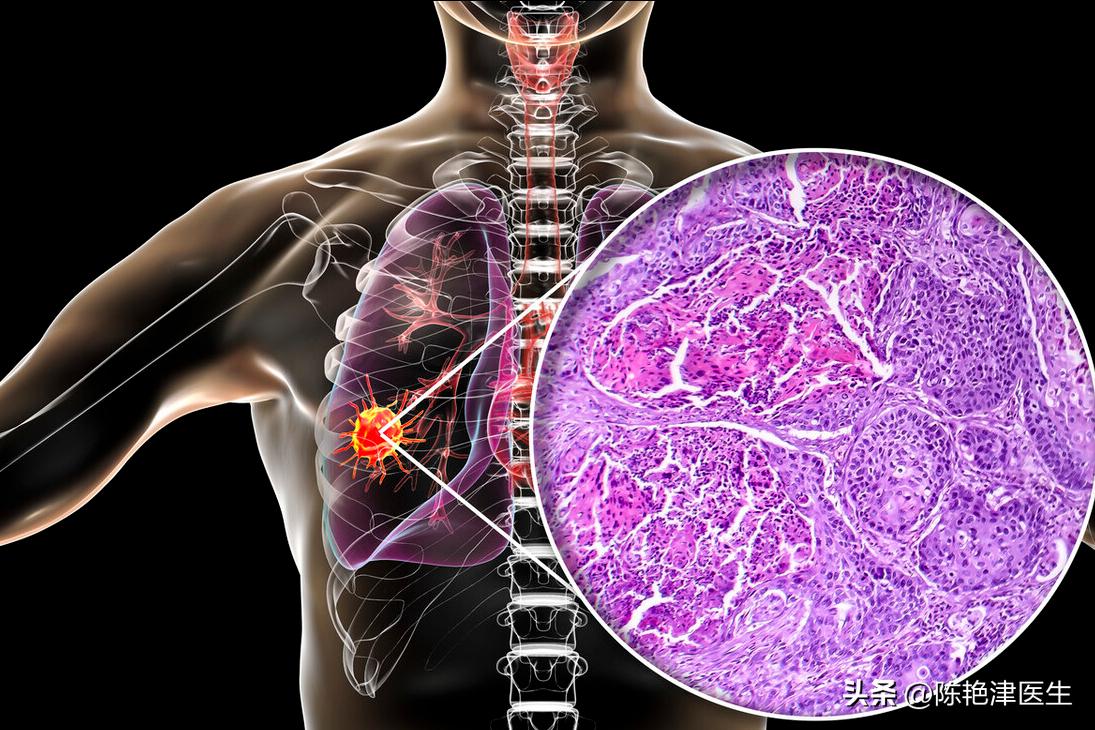

在组织切片显示的 癌细胞 在病变部位混乱排列形成乳头状、条状等各种形状的结构,并且逐渐向周围或者更深处扩散。

2. 肺鳞癌

肺鳞癌大约占肺癌发生率的50%,主要是发生在 支气管 部位的中央型肺癌。

肺部与空气接触的器官,容易接触外界的有害物质而病变。其中的 支气管覆盖有鳞状上皮细胞。